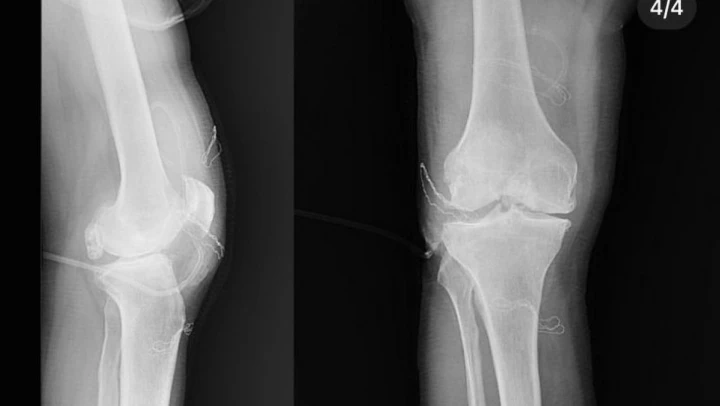

Diz ağrısı şikayeti ile geldiği Düzce Üniversitesi Tıp Fakültesi Hastanesi'nde ameliyata alınan hastanın dizlerinden toplam 41 adet multipl sinovial kondromatozisi çıkartıldı. Özellikle diz eklemi çevresinde görülmekle birlikte kalça, dirsek ve diğer eklemlerde de görülen, ufak parçalardan oluşan cisimler olarak tanımlanan eklem faresi, eklem çevresinde eklem sıvısı ya da sinoviyumda görülen kıkırdak ya da kemik parçalarıdır. Eklem farelerinin boyutları birkaç milimetreden birkaç santimetreye kadar çıkabiliyor.